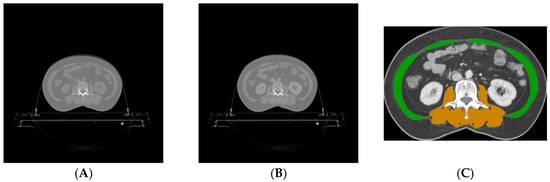

2.5.1. Preprocessing

2.5.2. Abdominal Muscle Segmentation

2.5.3. Paraspinal Muscle Segmentation